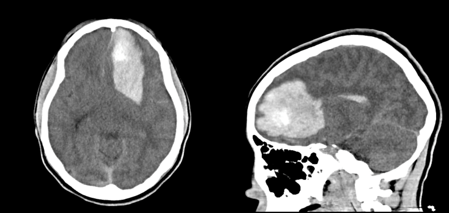

A 14 yo F with no past medical history presents to the ED after acute onset of headache, nausea/vomiting and change in mental status. Exam is significant for pupils 4mm b/l, equally reactive, but sluggish. She withdraws all extremities to pain. Accucheck is 149. A CT head is done and shown below. What's the diagnosis? (scroll down for answer)

Answer: Spontaneous left frontal ICH (intracerebral hemorrhage)

- CT scan is optimal imaging study for demonstrating hemorrhage and possible extension into the ventricles